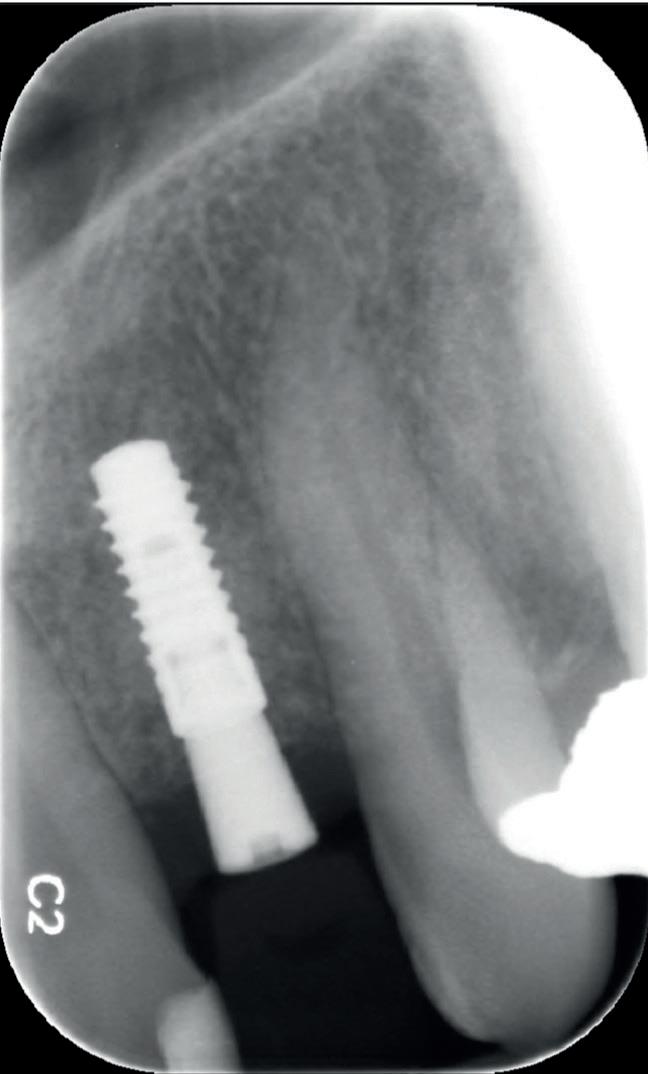

Bij klinisch en röntgenologisch onderzoek viel echter op dat radix van de 12 en 22 een convergerende (de radices staan dan naar mesiaal en naar elkaar toe) in plaats van divergerende (radices staan dan van elkaar af) stand had. Door deze convergerende stand van de radices was er in mesio-distale zin geen ruimte voor twee implantaten ter plaatse van de 11 en 21. Er werd daarom besloten, in tegenzin

1. Retainer met twee frontelementen

2. OPT radices 12 en 22 convergeren

3. Vaste apparatuur voor torque 12 en 22

4. OPT radices 12 en 22 divergeren na orthodontische behandeling

van de patiënt, om eerst weer vaste apparatuur terug te plaatsen om de radices in een divergerende stand te plaatsen. Gelukkig verliep deze behandeling voorspoedig. (afbeelding 2 -4). Het volgende behandelplan werd gemaakt: